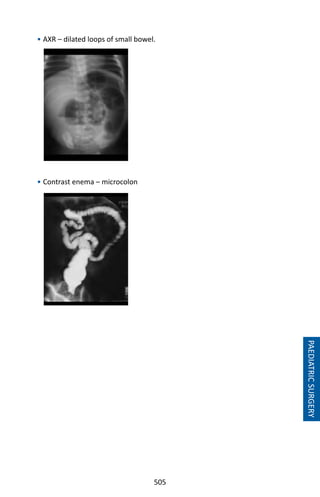

• 528.

515 Chapter 97: TheAcute Scrotum Causes of Acute Scrotum Acute testicular torsion. Torsion of epididymal and testicular appendages. Epididymo-orchitis. Incarcerated inguinal hernia. Idiopathic scrotal oedema. Acute hydrocele. Henoch-Schonlein purpura. Tumours. Trauma. Scrotal (Fournier’s) gangrene. Symptomatic varicocele. TORSION OF THE TESTIS Torsion of the testis is an emergency as failure to detort testis within 6 hours will lead to testicular necrosis. Symptoms • Sudden severe pain (scrotum and referred to lower abdomen) • Nausea and vomiting • No fever or urinary tract infection symptoms until later Physical Findings • Early • Involved testis - high, tender, swollen. • Spermatic cord – swollen, shortened and tender. • Contralateral testis - abnormal lie, usually transverse. • Late • Reactive hydrocele. • Scrotal oedema. There are 2 types of torsion: Extravaginal • The torsion usually occurs in the perinatal period or during infancy and is thought to be probably due to an undescended testis. Intravaginal • This is due to a high investment of tunica vaginalis causing a “bell-clapper” deformity. It usually occurs in boys between 10-14 years old. The deformity is usually bilateral. PAEDIATRICSURGERY

• 529.